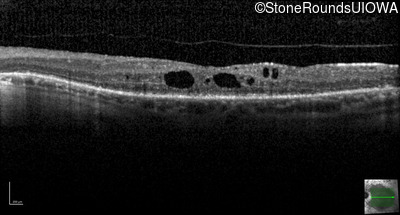

Optical Coherence Tomography - Left - 20/40 -1

Exemplar / OCT Stack

OCT Stack